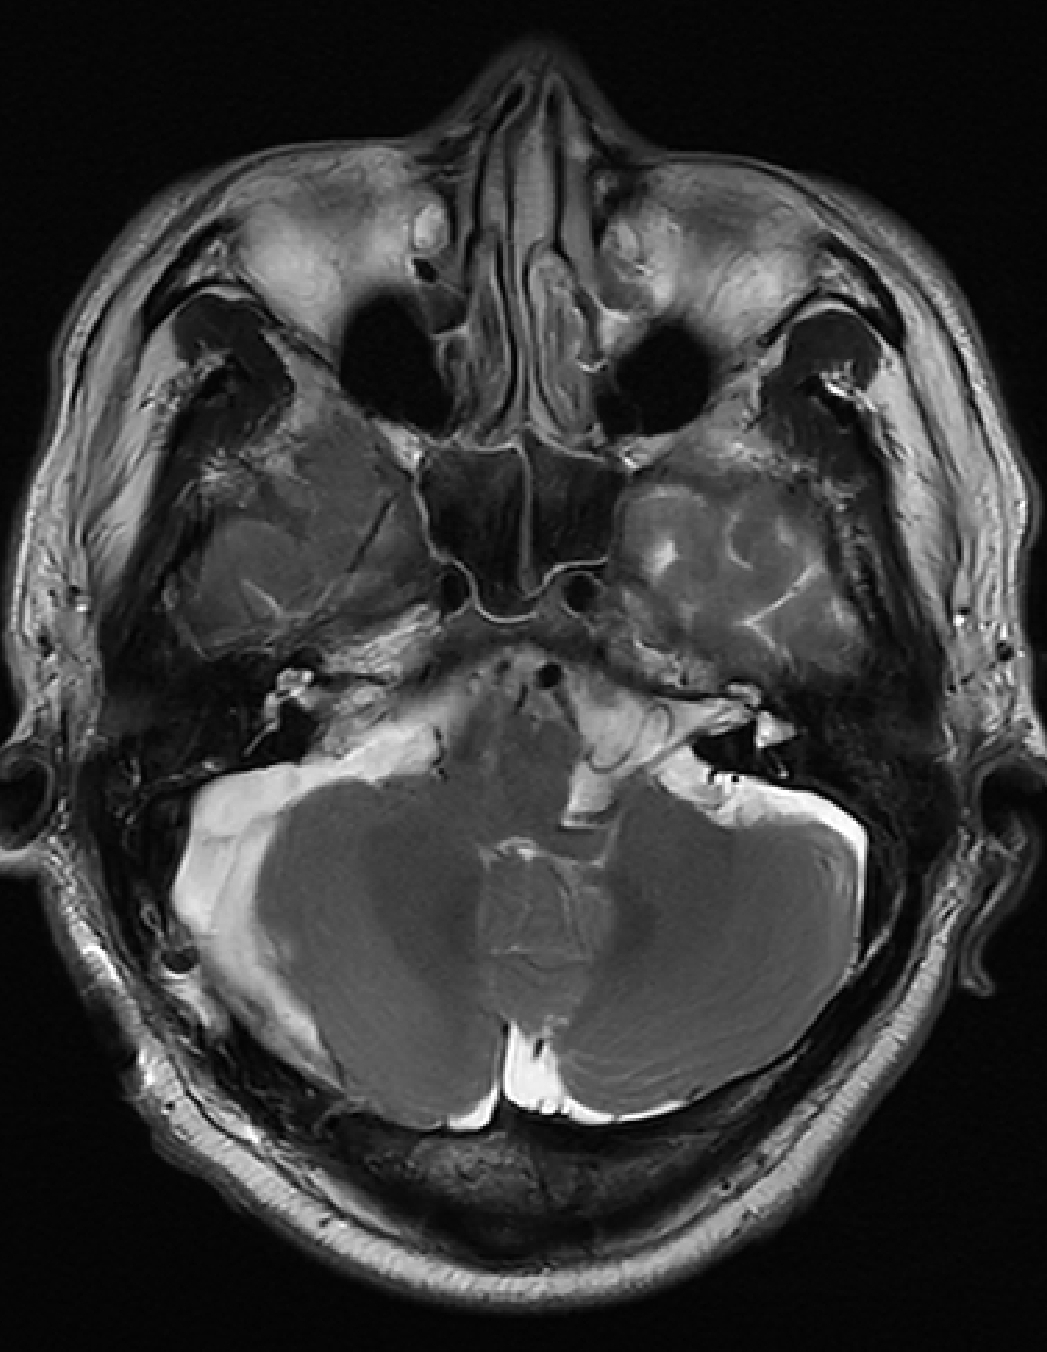

男性,58岁,右侧听力下降4年,突发晕厥后发现右侧桥小脑角占位,查体:右侧1-2级面瘫,右侧听力障碍

右侧桥小脑角3厘米占位,内听道扩大,肿瘤血供丰富,上方达天幕,与脑干关系密切,蛛网膜间隙不明显,颈静脉球相对高位,诊断考虑:右侧前庭神经鞘瘤(听神经瘤)